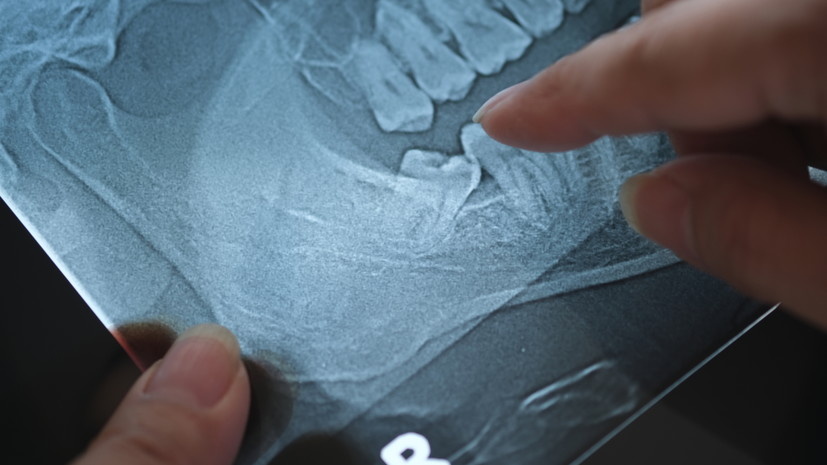

Стоматолог-имплантолог кандидат медицинских наук Игорь Кузьмин заявил, что удаление здоровых зубов мудрости без показаний не имеет медицинского смысла. «Если зуб прорезался полностью, стоит ровно, доступен для гигиены и не вызывает боли или воспаления, то с медицинской точки зрения он ничем не отличается от любого другого зуба», — заявил эксперт в беседе с Lenta.ru. По словам специалиста, удаление любого здорового зуба является хирургической операцией и может сопровождаться осложнениями, включая воспаление лунки, длительное заживление и повреждение нерва. Ранее почётный президент Стоматологической ассоциации России (СтАР) Владимир Садовский в беседе с НСН дал рекомендации по выбору клиники.